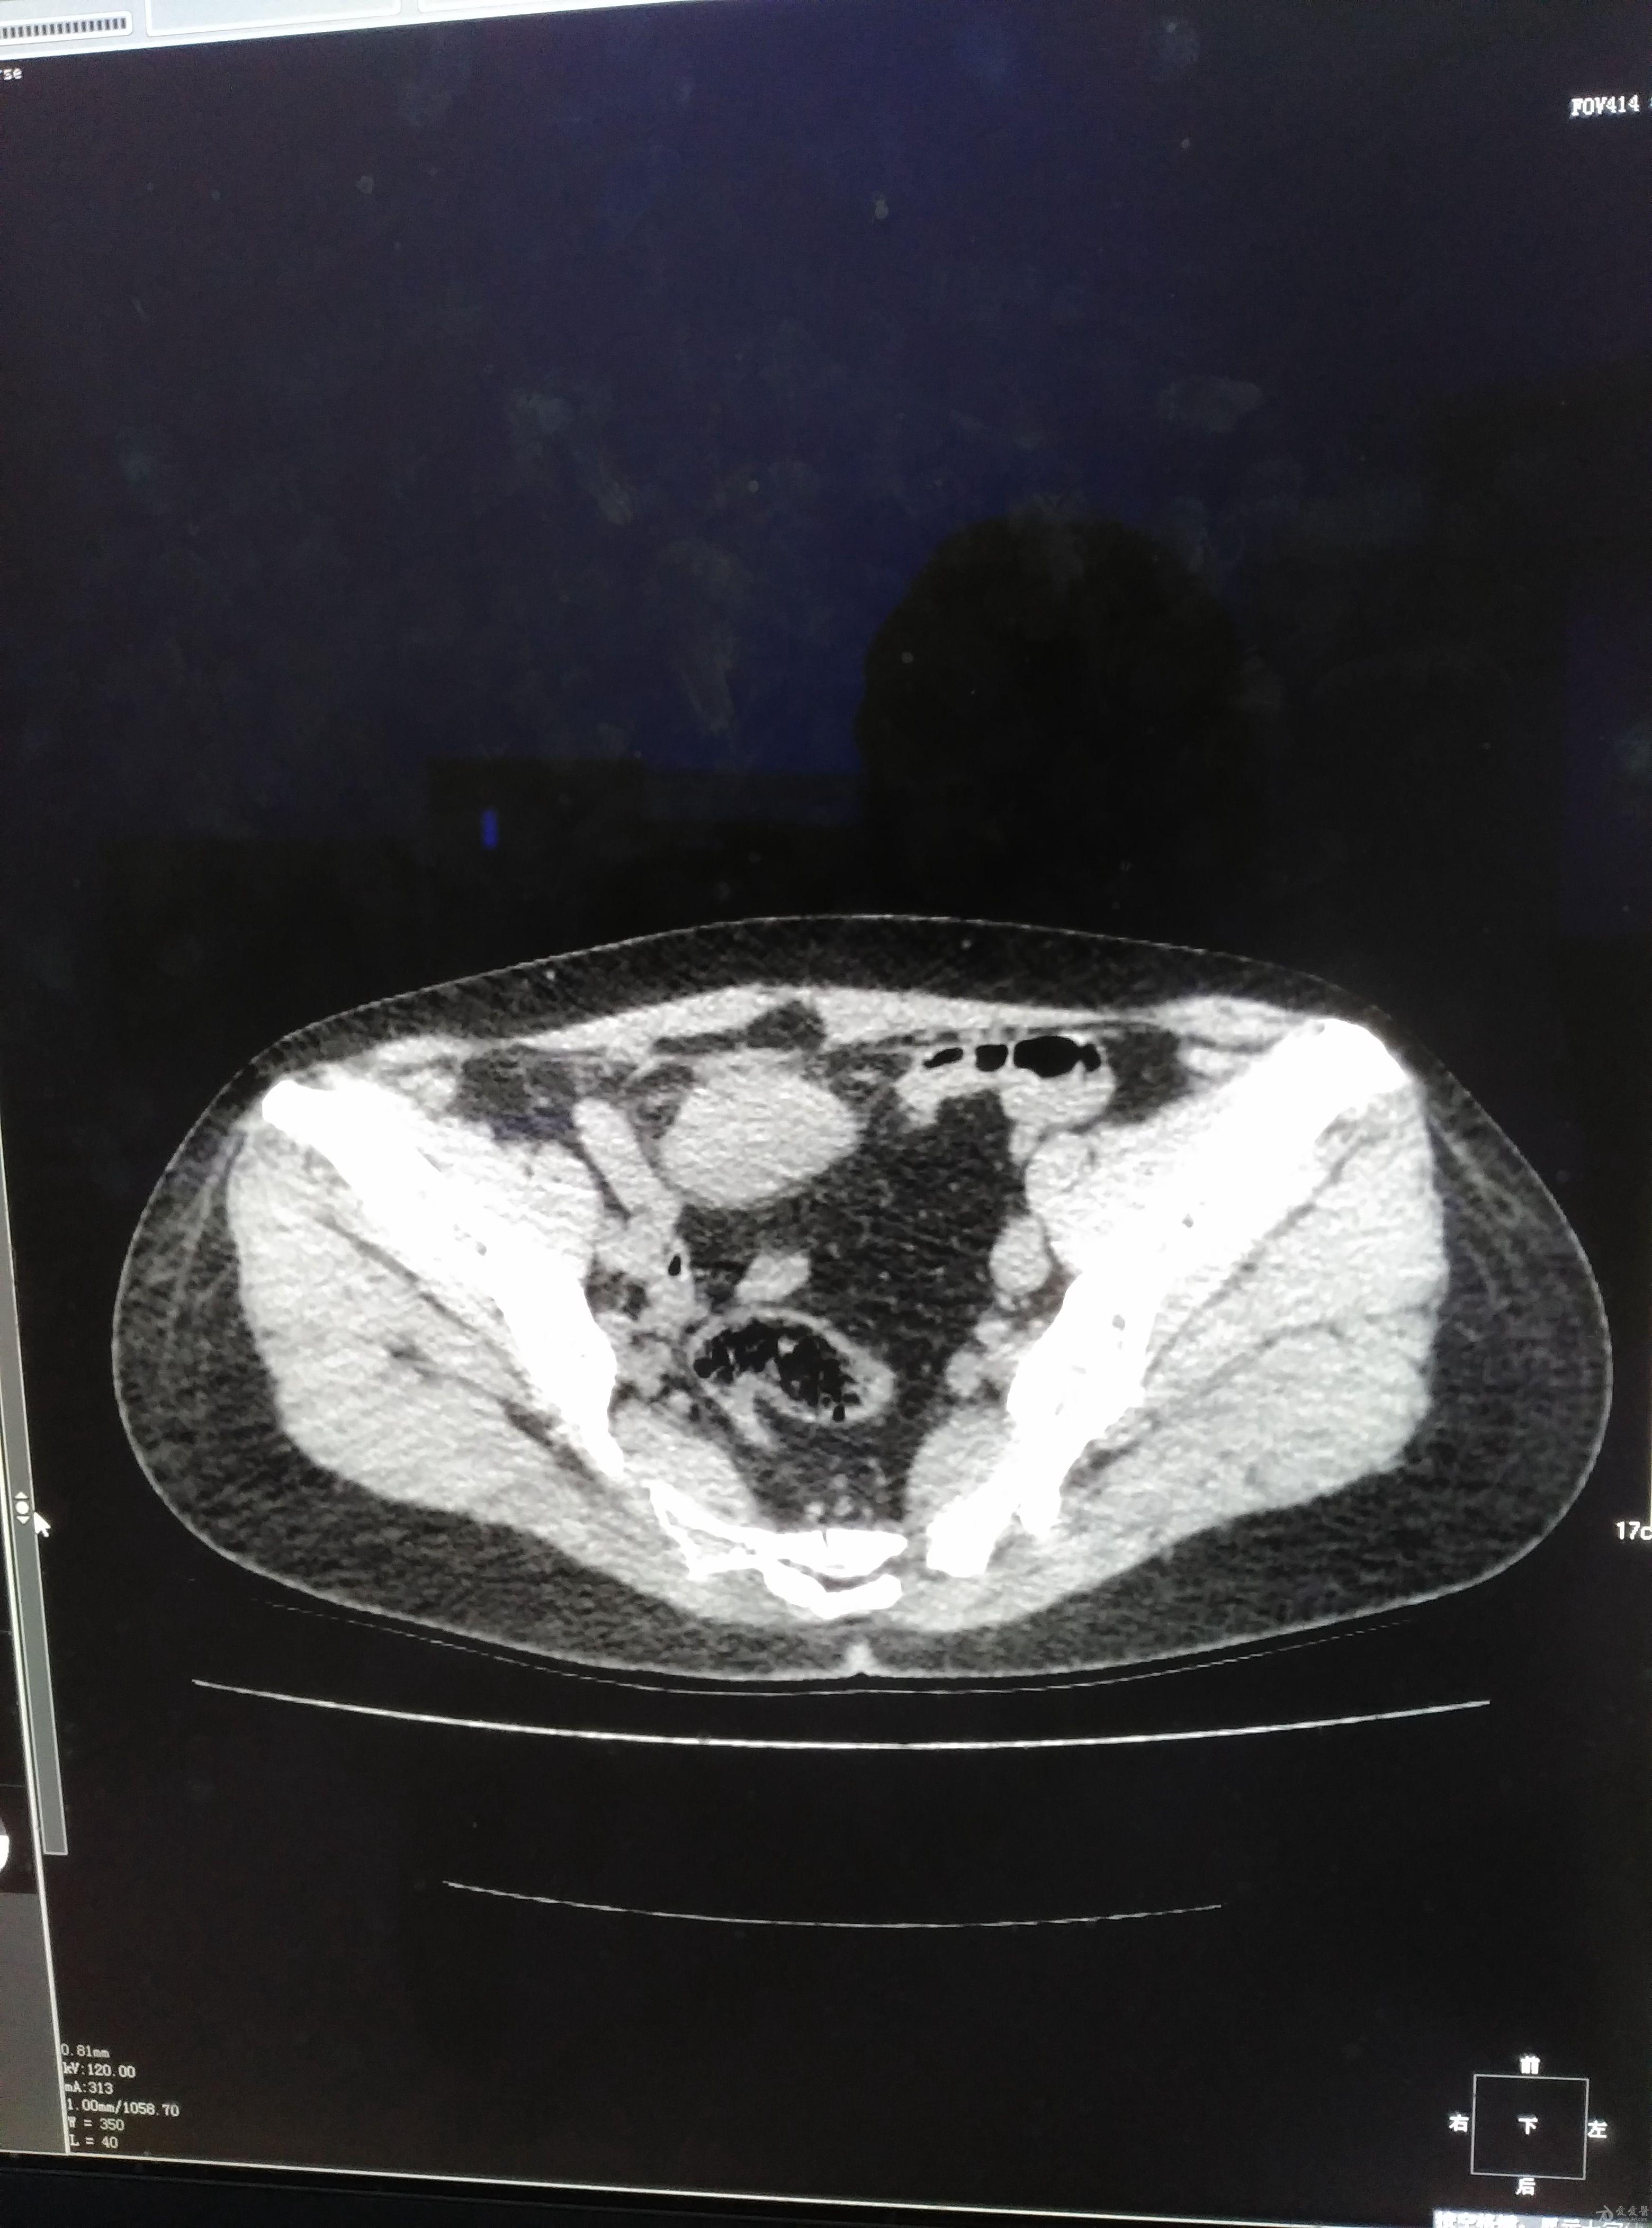

[腹盆] 腹部包块,女,53岁